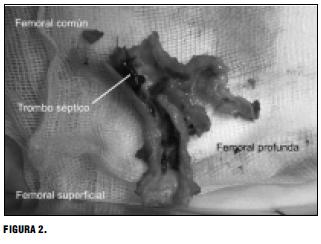

Luego del cierre esternal se realiza el abordaje amplio del eje iliaco femoral izquierdo (incisión inguinocrural y de fosa iliaca interna por vía extraperitoneal), y se resecan las arterias comprometidas, sustituyendo el trípode femoral por un segmento de arteria criopreservada. FIGURA 2

El trombo séptico de arteria femoral cultiva enterococo sensible a ampicilina sulbactam.

El trombo séptico impactó en la arteria femoral ateromatosa, diseminando la infección por los vasa vasorum, desarrollando periarteritis y absceso periarterial.